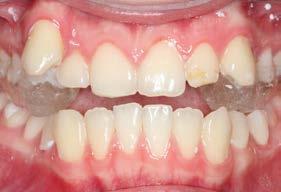

Figura 3. Lateral derecha. Figura 4. Izquierda de inicio. Figura 5. Frente. Figura 6. Overjet, laterales derecha e izquierda.

Las fotografías intraorales muestran las relaciones molares clase II y las relaciones caninas clase II bilaterales (Figura 3 y 4), espaciamiento anterosuperior, un overjet y overbite aumentado (Figura 5). La forma de los arcos es cuadrada, superior e inferior, con el apiñamiento moderado inferior y los espacios en superior.

Se planteó la corrección del perfil facial, corrección de las relaciones esqueléticas, corrección de overjet, overbite, del apiñamiento mandibular y cierre de espacio anterosuperiores; obtención de la clase I molar y canina bilateral, realizar las exodoncias de los terceros molares 18, 28, 38 y 48. Se realizó en una fase prequirúrgica de alineación, nivelación, (descompensación dental), tripodismo (estabilidad oclusal) utilizando brackets Roth .022 × .028, bandas en 6's y 7's

superiores e inferiores y vástagos quirúrgicos (Figura 6).